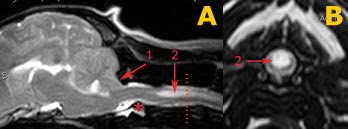

DIAGNOSI: L’unico esame che può confermare la diagnosi di siringomielia è la Risonanza Magnetica.

CANE RM SIRINGOMIELIA :

CANE RM NORMALE: